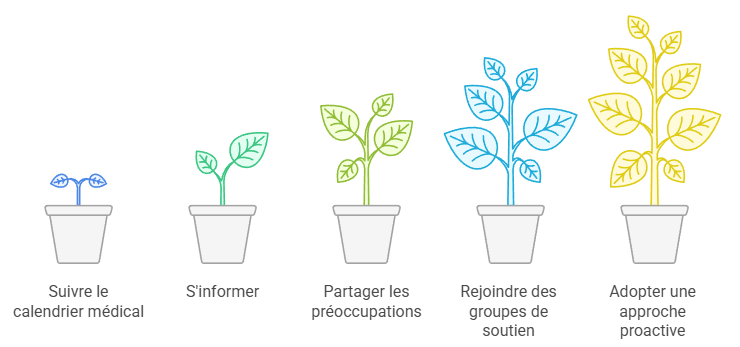

- Respectez scrupuleusement votre calendrier de suivi médical

- Informez-vous auprès de sources fiables sur votre condition

- Partagez vos préoccupations avec votre équipe médicale

- Rejoignez des groupes de soutien pour échanger avec d’autres personnes dans votre situation

- Adoptez une approche proactive dans la gestion de votre santé

Nous avons constaté que de nombreuses femmes trouvent réconfort et force dans le partage d’expériences avec d’autres personnes confrontées à des défis similaires. Les groupes de soutien, qu’ils soient en ligne ou en personne, peuvent offrir non seulement un soutien émotionnel précieux, mais aussi des conseils pratiques pour naviguer dans le système de soins de santé et gérer les aspects quotidiens de la vie avec des nodules pulmonaires.